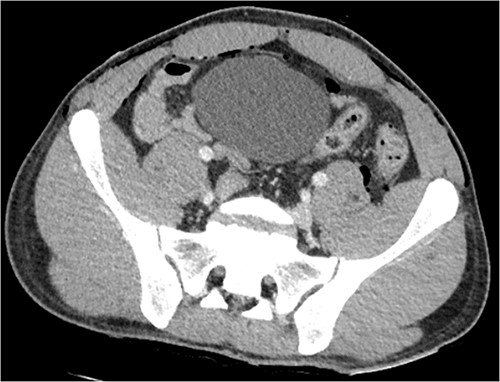

Following extubation, bilateral chest wall subcutaneous emphysema was noted extending to the neck. He also complained of central chest discomfort, without respiratory distress, oxygen desaturation or airway obstruction. Chest X-ray (CXR) revealed pneumomediastinum and surgical emphysema in the lateral chest walls bilaterally. Computed tomography (CT) of the chest, abdomen and pelvis demonstrated large volume subcutaneous emphysema bilaterally in the scrotum, abdominal and chest walls extending to the neck (see Figs 2–5). Gas was noted between the abdominal muscle layers, extraperitoneal and retroperitoneal spaces without pneumoperitoneum (see Figs 5–6). Moderate pneumomediastinum was prominent within the superior and antero-inferior mediastinum without evidence of tracheal or oesophageal injury and an associated small left pneumothorax was noted (see Figs 1–3).

CT abdomen and pelvis axial, left retroperitoneal gas locules overlying iliopsoas muscle.